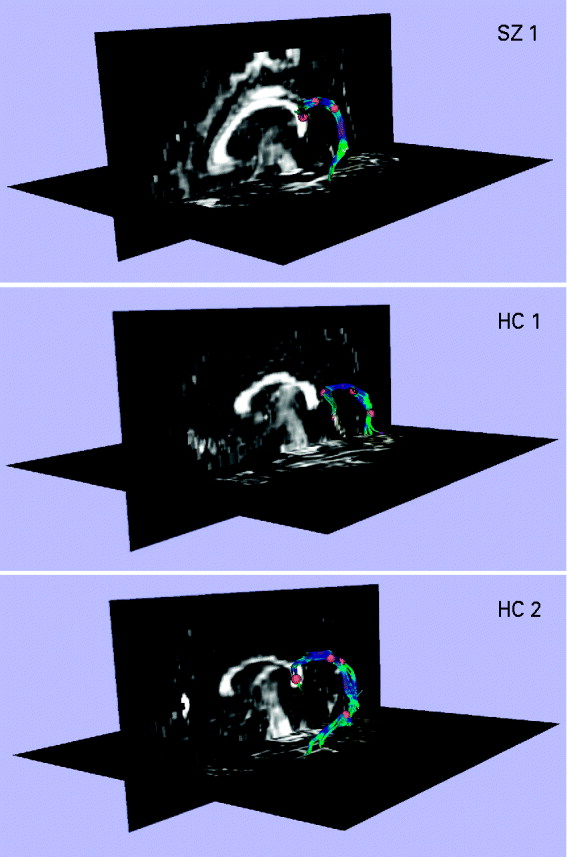

Extraction of the arcuate fasciculus

Fig. 1. Extracting the left arcuate fasciculus from participants' diffusion tensor (DT) images with deterministic (streamline) tractography. The extracted arcuates of three representative participants, one patient with schizophrenia (SZ) and two healthy controls (HCs), are shown overlaid onto a sagittal and axial slice of their fractional anisotropy (FA) image. The first step in the tractography procedure involved manually placing a cubic region of interest (i.e. a fiducial) of side 3.5 mm in the dorsal longitudinal fibers of the arcuate fasciculus, according to the protocol of Catani et al. (Reference Catani and Thiebaut de Schotten2008). The voxels defined by this fiducial were then used as seedpoints for deterministic (streamline) tractography, which followed the direction defined by the principal eigenvector. A step size of 1.5 mm was used, and tractography was terminated upon reaching a voxel of FA <0.25 (the stopping criterion). The small number of voxels defined by the fiducial meant that immediate feedback was available as to the legitimacy of the fiducial's location. The spatial position of the fiducial was then adjusted until the distinctive ventrally projecting, curved fibers of the arcuate fasciculus became apparent. Additional fiducials (typically between 1 and 3) were then placed along the length of the arcuate to augment the fiber bundle. The fiducials for all participants were placed by a single rater who was blind to subject diagnosis.